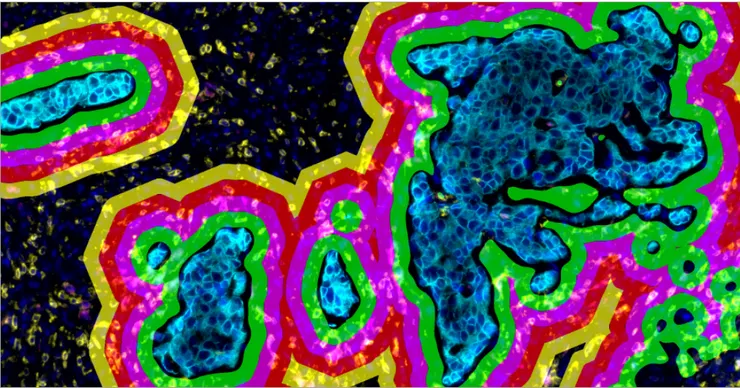

空間生物學(spatial biology)是一門快速發展的學科,它使研究人員能夠在組織微環境中精確觀察和分析生物分子(如 RNA、蛋白質、代謝物等)的空間分佈。 這種方法突破了傳統組織學只能提供形態學資訊的局限性。

- 在腫瘤微環境中識別與藥物反應和預後相關的空間生物標記

- 解析免疫細胞與癌細胞之間的複雜互動機制